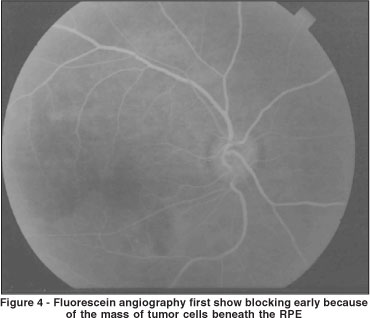

The left eye ocular fundus was normal. Fluorescein angiography (FA) of the patient's right eye revealed first show blocking early because of the mass of tumor cells beneath the RPE. The blocking is especially apparent in the macula where the mass appears to be thickest (Figure 4).

The blocking is of the choroidal fluorescence and because the cells lie in front of the choroid. Then the FA shows late leakage from breakdown of the outer blood retinal barrier, again due to the infiltration of the tumor cells (Figure 5). Fluorescein angiography of the left eye was normal.